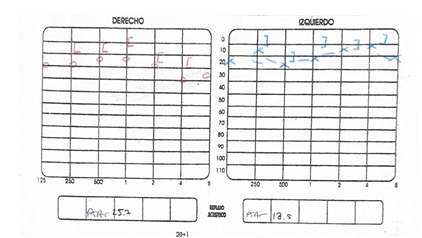

La paciente fue sometida a una resección quirúrgica por abordaje retroauricular, la lesión se encontraba limitada a la pared anterior del CAE coincidiendo con los hallazgos radiológicos preoperatorios. Se realizó una incisión retroauricular 1 cm por detrás del pliegue retroauricular, con hoja de bisturí #15 se diseca por planos hasta llegar a músculo auricular posterior, el cual se corta y se identifica mediante palpación pared superior e inferior del conducto auditivo externo, se realiza colgajo de Palva y se identifica espina de Henle, área cribosa y sutura timpanomastoidea, se accede a través de dicho colgajo a la piel de la pared posterior del CAE en la cual se realiza incisión cefalocaudal de 1 cm para lograr una exposición completa del CAE y se sostiene el colgajo utilizando un separador dentado. Se visualiza lesión y se elevan colgajos epiteliales superior e inferior al borde más lateral de la lesión, exponiendo de esta manera la cortical de la lesión. Con drill quirúrgico se fresa desde el centro de la lesión hasta quedar únicamente la cortical, obteniendo un “cascarón de huevo”, posteriormente se observa el pedículo de la lesión y se fractura, retirando por completo la lesión ósea, y se fresa la base de la lesión para evitar recurrencia. Posterior a la resección quirúrgica se realiza aseo del CAE, con antibiótico y esteroide, extrayendo restos celulares y se comprueba integridad de la membrana timpánica, se feruliza con Silastic y gelfoam impregnado con corticoide y antibiótico. La paciente presentó una adecuada evolución audiológica corroborada por audiometría tonal, la cual demostró normoacusia en el oído intervenido. Durante las citas postquirúrgicas se evidenció una adecuada cicatrización de tejidos retroauriculares así como los colgajos epiteliales del conducto. La evolución quirúrgica fue favorable, al mes se encontraba asintomática y la audiometría de control reporta normoacusia bilateral. (Figura 5).

| (Figura 5). Audiometría con normoacusia bilateral. |